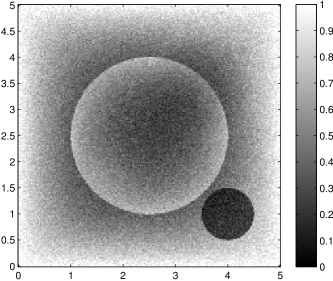

The data (see Figures 1 and 2) was generated in the diffusion model (1.2) using self-written (linear-basis) finite element code in MATLAB. For both examples, we took and used a uniform boundary condition . The simulated data were generated on a -grid and then down-sampled (by averaging) to to avoid inverse crime. After that, Gaussian noise with different intensities (standard deviations of and of the average signal value ) was added to the data.

The edge detector is used to detect jumps in the derivatives of the data up to second order (to obtain an initial estimate of the parameter jump set ). Since this process is highly sensitive with respect to noise, we varied the edge detection procedure subject to the amount of noise in the data. In the noise-free examples, we estimated the jumps of all three functions , that is, jumps of derivatives of up to second order. We restricted the jump estimation to for the low-noise examples (i.e., jumps of derivatives up to first order) and in the high-noise examples (only jumps in the data itself).

Reconstruction results and error profiles at different noise levels can be seen in Figures 3 and 4. In both examples, the noise-free reconstructions are very accurate and contain mostly smoothing error. In the low-noise reconstructions, due to the fact that more regularization is necessary, some of the parameter variation is underestimated. In the high-noise examples, most detail in is lost since a lot of regularization is required to get reasonable results. The fine detail in can, however, still be recovered very accurately in both examples.